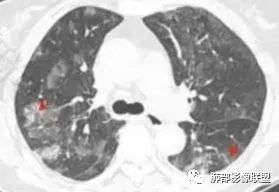

6.间质性改变:多位于病灶周围,可见边缘磨玻璃密度影或晕征及树芽征象,周围组织间质增厚并且有结节感,病理基础为肿瘤细胞浸润细支气管周围间质及肺泡壁。

磨玻璃影及间质小结节影